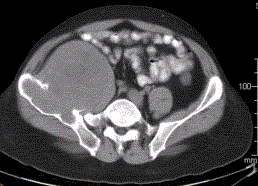

患者男,28岁,右下腹及臀部疼痛5个月余。查体:右髂骨外后侧压痛,右下腹可触及一软组织包块,质韧,固定。行骨盆正位CR、骨盆CT及MR扫描见下图。...

问题 患者男,28岁,右下腹及臀部疼痛5个月余。查体:右髂骨外后侧压痛,右下腹可触及一软组织包块,质韧,固定。行骨盆正位CR、骨盆CT及MR扫描见下图。 关于病变发生的部位,叙述正确的是

选项 A.右髂骨皮质部,累及右侧腰大肌 B.右髂骨髓质部,累及右髂骨皮质及右侧腰大肌 C.右侧腰大肌,累及右髂骨 D.盲肠,累及右髂骨 E.末段回肠,累及右髂骨

答案 B